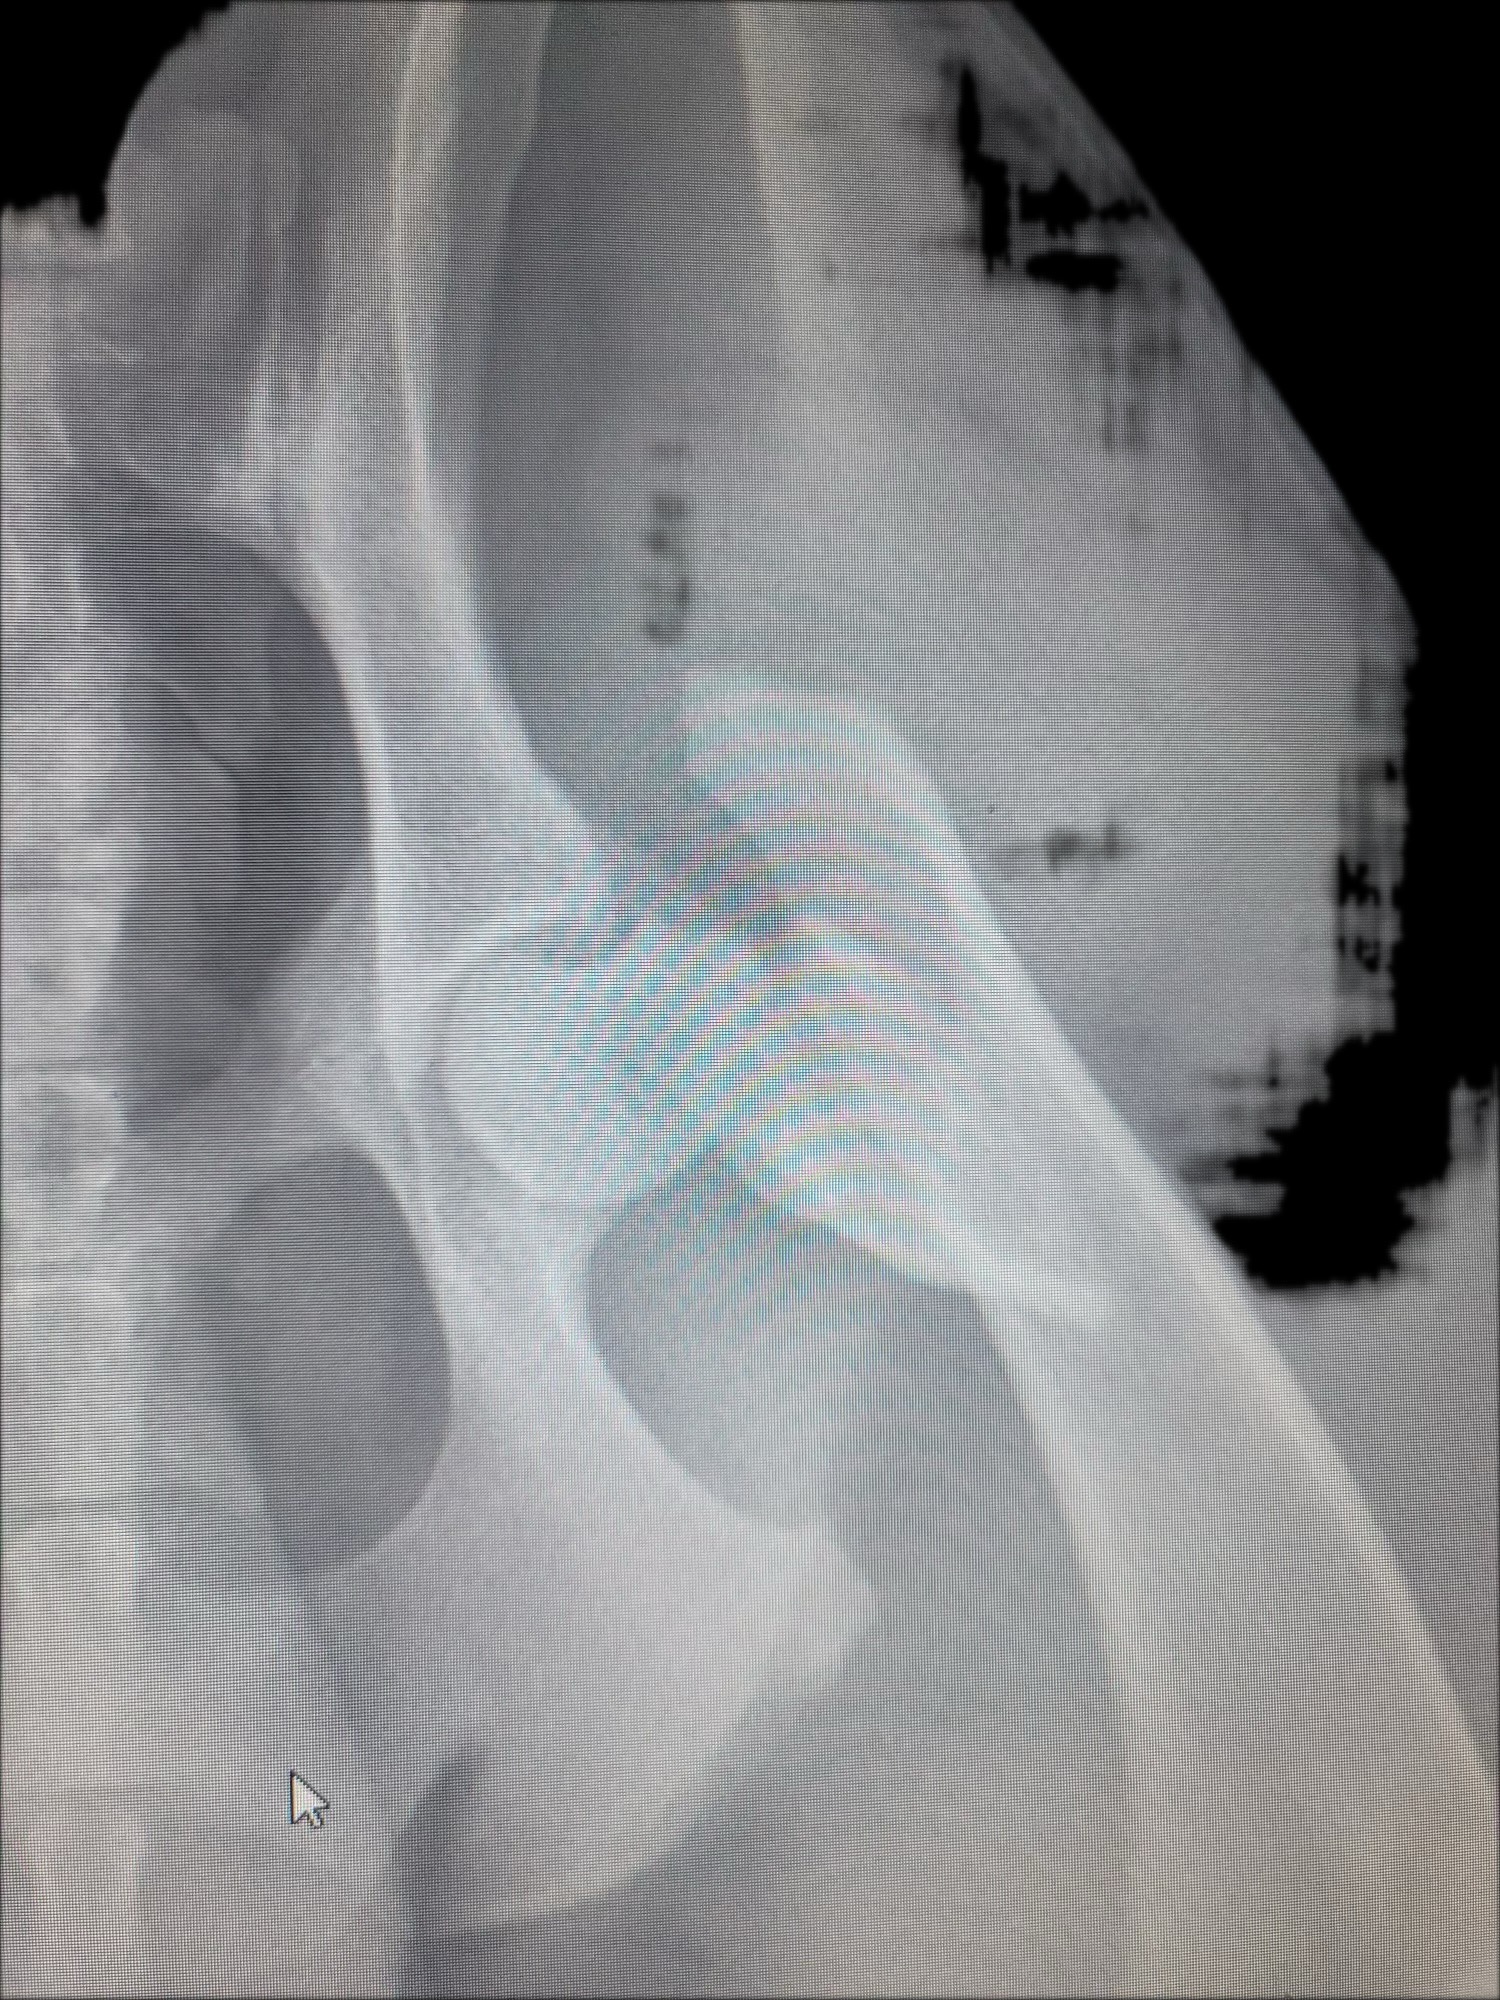

Hello, my name is April and I’m an animal lover and a caregiver for the elderly. This beautiful young dog we decided to name Ace came to us with his friend. It looks like he got his injuries from getting hit by a car on Sunday, 9-7. We held the dog in a dog run until animal control was called. They never came on Sunday. I called Monday morning, and they said the shelters are over capacity and that to ensure the dogs would survive, I could foster. I told them yes, but the injured one would need to be seen for his injuries and that I would foster when the three-day hold on the dog was up. During those three days, I learned the only thing they did for him was give pain meds and take x-rays. No other treatment was done.

Friday, September 12, was the last day of the hold, and I was able to go pick him up that morning. Since no rescues stepped in to get him, I took him to our local vet, who I talked to the previous days for an appointment. The second I was able to get him out of the shelter, we went over a plan on how to help him. As of now, we have surgery planned for Tuesday, September 16. Ace is said to be a year and a half and is a happy, outgoing dog. He was so excited to see me and has a fight to survive, so I promised to do what I can to help him. We’ve made it this far and are praying to have everyone come together to help this beautiful, amazing, happy, outgoing dog Ace get fixed and give him a chance at a happy, full life. Thank you so much for your support and kindness.